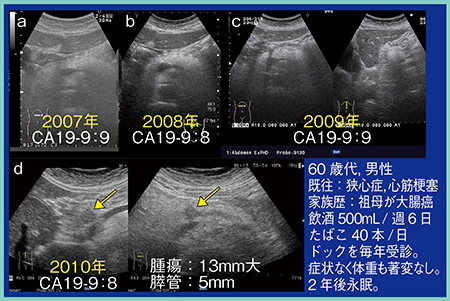

症例1は,60歳代,男性。2007年から毎年ドックを受診していたが,2010年の検診にて腫瘍径13mmの膵癌を指摘された(図7 d)。発見時には症状はなく,体重の著変も見られなかったが,2年後に永眠された。膵癌の進行は非常に早く,1年ごとの検診では間に合わないこともある。

図7 症例1:がんドック発見膵癌